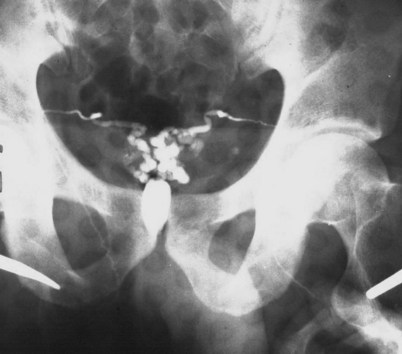

If a large amount of fluid is found in the vasal lumen and microscopic examination reveals the presence of sperm, the obstruction is toward the seminal vesicle end of the vas. In these cases the vas is usually markedly dilated. A 2-0 Proline suture can be passed toward the seminal vesicle end of the vas and a clamp placed on the Proline when the suture passes no farther. This is particularly useful for delineating the site of inguinal obstruction from prior groin surgery. If the obstruction is proximal to the inguinal scar, formal vasography is performed by passing a No. 3 whistle-tip ureteral catheter toward the seminal vesicle end of the vas. A 16-Fr Foley catheter is placed in the bladder, and the balloon is filled with 5 mL of air. Placing the balloon on gentle traction before vasography prevents reflux of contrast into the bladder, which can obscure detail (Fig. 22–5). The air-filled balloon also identifies the location of the bladder neck relative to any obstruction. After the vasa have been cannulated, vasograms are performed with the injection of 0.5 mL of water-soluble contrast media (Fig. 22–6). If vasography reveals obstruction at the site of the ejaculatory ducts (Fig. 22–7), indigo carmine is injected in both vasa to assist a transurethral resection (TUR) of the ejaculatory ducts (see Diagnosis later). If both vasa are visualized after injection of contrast into only one vas (Fig. 22–8), it means both vasa empty into a single cavity, usually a midline ejaculatory duct cyst.

Figure 22–5 Placing the balloon on gentle traction before vasography prevents reflux of contrast into the bladder, which can obscure detail.

Figure 22–8 Both vasa are visualized after injection of contrast into one vas only, revealing distal obstruction.